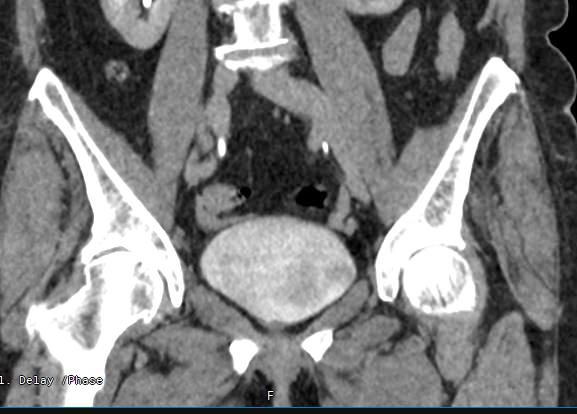

Мультиспиральная компьютерная томография органов малого таза включает в себя исследование женских половых органов (матка, яичники) или мужских половых органов (предстательная железа, семенные пузырьки, семявыносящие протоки), а также мочевого пузыря с мочеточниками на видимом протяжении, прямой кишки, тазовой брюшины, лимфатических узлов, мягких тканей малого таза.

Нативная компьютерная томография таза проводится без использования контраста. Однако при подозрении на патологические изменения со стороны органов мужской или женской половой сферы, мочевыделительной системы, прямой кишки или окружающих мягких тканей, обязательным является внутривенное введение йодсодержащего контрастного препарата. Контрастный препарат в большей степени накапливается в патологически измененных участках и обеспечивает их яркую визуализацию на фоне здоровых тканей. Это используется для диагностики онкологических заболеваний на ранних стадиях, что имеет решающее значение для жизни и здоровья пациента.

В результате получаются снимки тончайших срезов исследуемой зоны с высокой степенью детализации, на основе которых производится объемная реконструкция органов малого таза, что позволяет проводить точную диагностику. Трехмерные модели дают информацию о пространственном расположении органов и патологических образований, что важно, например, при планировании оперативных вмешательств и в дальнейшем при оценке эффективности операции и проведенного лечения.

Мультиспиральная компьютерная томография используется для диагностики аномалий развития, травматических повреждений, воспалительных заболеваний и опухолевых процессов органов малого таза. Преимуществами данного исследования является высокая скорость сканирования и доступная цена. Однако в ряде случаев может быть более предпочтительно выполнение магнитно-резонансной томографии, которая обладает высокой чувствительностью и информативностью для обследования органов и мягких тканей малого таза. В клинике «Доступная медицина» МРТ малого таза можно пройти на нашем современном оборудовании экспертного уровня.